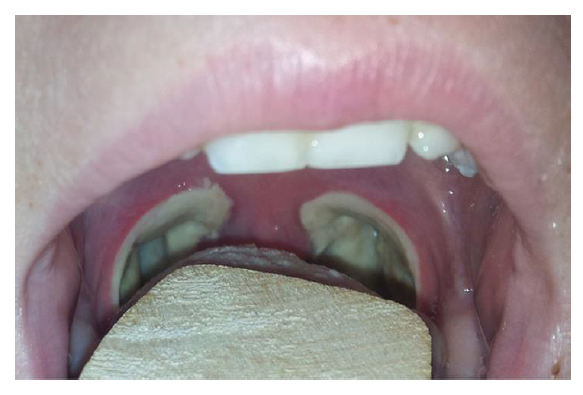

Typical post-operative appearance on day three.